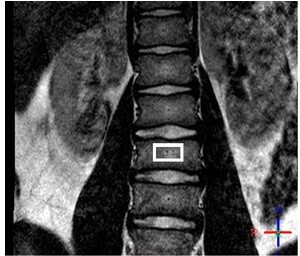

Исследования жирового состава костного мозга, принимающего участие в процессах кроветворения и системного обмена веществ, являются второй по распространенности областью применения МР методов определения фракции жира. Так, ряд исследований продемонстрировали обратные зависимости между параметрами фракции жира и минеральной плотностью костей у пациентов с остеопорозом и остеопенией [18-19]. Аналогичный результат был получен в одном из совместных научных проектов Philips с НИИ Неотложной Детской Хирургии и Травматологии – чем выше содержание жира в позвонках у детей, тем ниже значения минеральной плотности. Более того, выявлено, что пациенты с более высокими значениями FF в большей степени подвержены риску травматизации при компрессионном переломе позвоночника [20]. Часть исследований утверждает, что жировые клетки участвуют в снижении костной массы за счет лептина, однако, более точные модели требуют дальнейших научно-клинических разработок. Помимо остеопороза и остеопении изменения в жировом составе костного мозга были выявлены у пациентов с диабетом [21]. Количественные значения PDFF могут использоваться как маркер относительного содержания красного и желтого костного мозга, которое может изменяться в случае злокачественной инфильтрации [22], а также заболеваний кроветворной системы. В одном из совместных с Philips научных проектов сотрудники отдела лучевой диагностики Национального Медицинского Исследовательского Центра Детской Гематологии, Онкологии и Иммунологии им. Дмитрия Рогачева обнаружили резкое снижение значений фракции жира у пациентов с острым лимфобластным лейкозом [23]. Дальнейшее изучение показателей PDFF в динамике химиотерапевтического лечения может позволить производить неинвазивную оценку эффективности проводимой терапии. Наряду с этим было обнаружено снижение значений PDFF в области острого воспалительного процесса у пациентов со спондилоартритом, для которых оценка воспалительного процесса является одной из первостепенных задач для наблюдения за развитием заболевания и эффективностью терапии. При этом, в хронической стадии значения фракции жира, наоборот, увеличиваются. Количественные методики оценки значений PDFF оказываются более воспроизводимыми, чем рутинные методы, основанные на визуальной оценке по Т1, Т2 иSTIR изображениям.